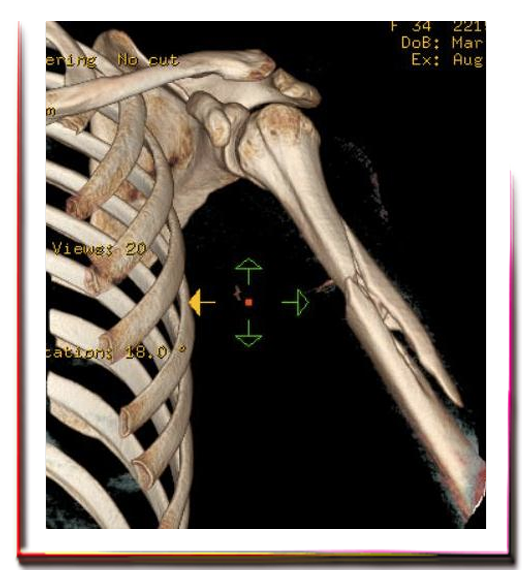

Humerus Kırıkları, tüm kırıkların %1'ini oluşturur. Ayrışma ya da belirgin parçalanma göstermemiş humerus kırıkları genellikle dengeli vasıftadır. Dengeli kırıklar ufak derecelerde açılanma gösterebilirler.

Önemsenmeyebilecek (çoğu farkedilmeyen) şekil bozukluklarına neden olurlar. Kollar, bacaklar gibi yük taşımadıkları için bu bozukluklar, kırık iyileşmesini ya da fonksiyonları önemli ölçüde etkilemezler.